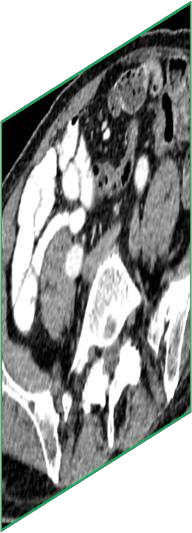

Due to the constraints of the imaging device and high cost in operation time, computer tomography (CT) scans are usually acquired with low intra-slice resolution. Improving the intra-slice resolution is beneficial to the disease diagnosis for both human experts and computer-aided systems. To this end, this paper builds a novel medical slice synthesis to increase the between-slice resolution. Considering that the ground-truth intermediate medical slices are always absent in clinical practice, we introduce the incremental cross-view mutual distillation strategy to accomplish this task in the self-supervised learning manner. Specifically, we model this problem from three different views: slice-wise interpolation from axial view and pixel-wise interpolation from coronal and sagittal views. Under this circumstance, the models learned from different views can distill valuable knowledge to guide the learning processes of each other. We can repeat this process to make the models synthesize intermediate slice data with increasing inter-slice resolution. To demonstrate the effectiveness of the proposed approach, we conduct comprehensive experiments on a large-scale CT dataset. Quantitative and qualitative comparison results show that our method outperforms state-of-the-art algorithms by clear margins.